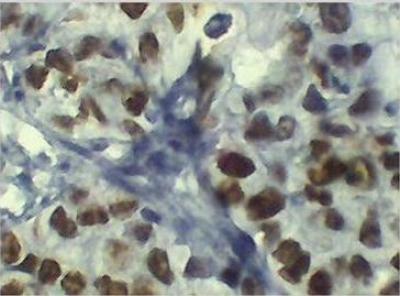

Expression of p53 Protein in Women within the Premenopausal Age

Figure 1: Positive (IHC) detection of p53 protein (A-D). Tissue with crisp brownish nuclear precipitatation of p53 protein overexpression; (A) S0045164, magnification x40, (B) S004776, magnification x10. (C) S0048960, magnification x10, and (D) S0047962, magnification x40